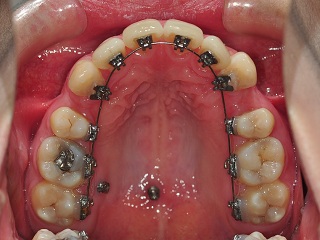

이번 월치료에서는 상악의 와이어교체와 하악 앞니에 보조장치를 부착하였어요.

지금 상악에 세 개의 치아에 치아교정장치 브라켓이 부착되어 있지 않은데요~

이것은

다음 치아교정 월치료에 다 부착하기로 했어요^^

그러고 나서 상악와이어 교체가 이루어졌구요